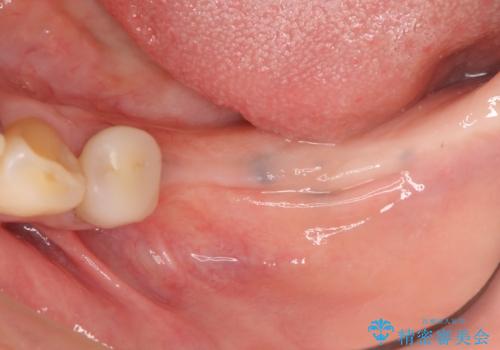

- 左下に長年使用した入れ歯が合わず、よりしっかりと噛みたいという希望で来院されました。

入れ歯をはずししっかりと噛む手段としてインプラント治療を進めていきます。